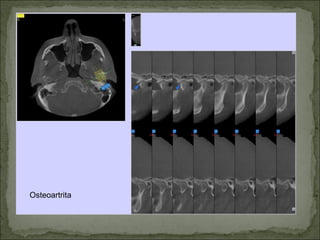

Osteoartrita